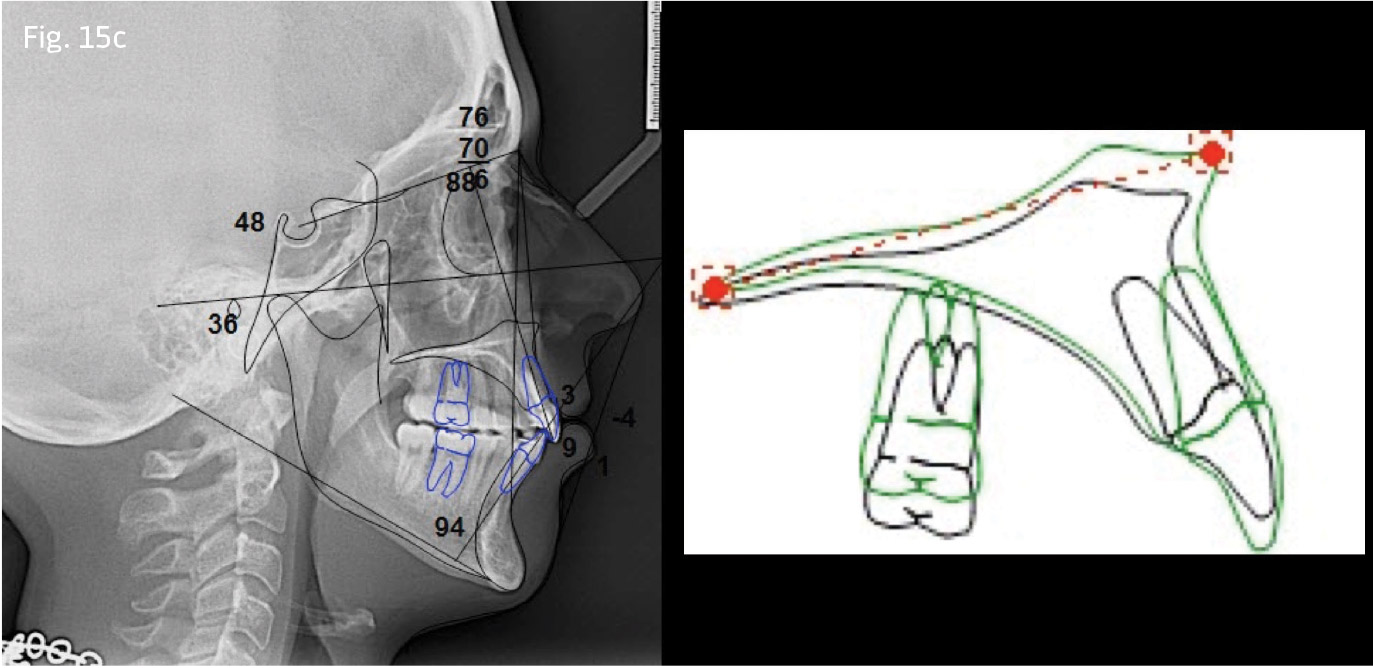

Upon bite closure in both cases, 19x25 titanium molybdenum alloy (TMA) wires were inserted, the TPA was removed and standard techniques were used for detailing and finishing (Figs. 14a–c, pg. 30 and 15a–c).

Treatment comparisons

In both cases, passive self-ligating brackets with standard anterior torque prescription were placed. Quarter-inch, 2-ounce posterior cross-elastics were used as needed from the lingual of the upper molars to the labial of the lower molars from the first archwire insertion of .014 copper nickel titanium (CuNiTi). The archwire sequence of 14x25 unit, 18x25 CuNiTi, 19x25 stainless steel was followed with 10-week appointment intervals. The posterior crossbite relationships in Case 1 were corrected before advancement to 18x25 CuNiTi. In Case 1, once both arches were worked to 19x25 stainless steel, a Rocky Mountain Orthodontics fixed/removable transpalatal arch was inserted into the vertical lingual sheaths of the upper molar bands, with 6mm of clearance relative to the palate (Fig. 12). In Case 2, molar bands were avoided by placing a bonded TPA bent from .036 stainless steel. It was bonded to the occlusal surfaces of the upper first molars (see Fig. 13). This prevents lingual rolling of the buccal segments during intrusion.